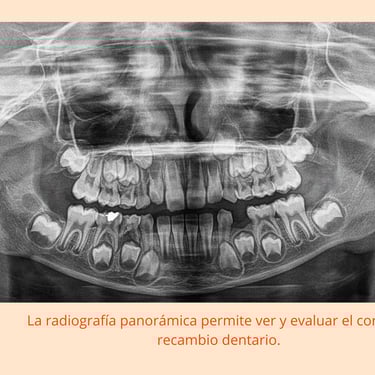

Radiografías: Se pueden tomar radiografías para evaluar los dientes que aún no han erupcionado.